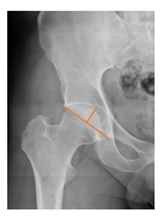

Plain radiographs were evaluated preoperatively and at the most recent follow-up, after appropriate calibration. Positional parameters were assessed according to values guidelines from published literature, as listed in Table 1 [23,24,25,26,27,28,29,30,31]. Femoral stem and acetabular cup osteointegration were quantified according to Engh [32] and Moore scale [33]. Heterotopic ossifications were graded according to the Brooker system [34].

Preoperative and postoperative radiographic data are reported in Table 4. Preoperatively, 18 THR (24.3%) were implanted in skeletally immature children with closed triradiate cartilage (1 ≤ Risser ≤ 3). Radiographic acetabular insufficiency (LCEA < 25° and AI > 13°) was detected in 14 hips (18.9%), while protrusion was present in 3 hips (4.1%) An excessive valgus of the femoral neck was observed in 19 hips (25.7%), while an important varus deformity was present in 7 hips (9.5%).

Postoperative radiographs showed a significant vertical malposition of the cup in 1 case (1.4%), a significant varus stem in 8 cases (10.8%) and a significant valgus stem in 1 case (1.4%). Two patients (2.7%) showed moderate heterotopic bone formation (Brooker ≥ 2), that did not significantly affect the hip motion and symptoms. All those THR that did not undergo revision showed good radiographic osteointegration, with no evidence of implant breakage, radiographic lucencies, bone defects, cup migration, or stem subsidence at the most recent radiographs.

In our experience, implant malposition was the only reason for implant revision. In one case, progressive subsidence was observed in a varus undersized stem, implanted in a boy with Albers–Schömberg disease; in another case, an excessively vertical cup with a 28 mm femoral head caused hip instability and required cup revision.

THR can be a challenging procedure in very young people. The combination of distorted anatomy, small physique, and poor bone stock can impede proper implant placement. Implant sizing may be an issue in these patients. The combination of young age and peculiar conditions such as skeletal dysplasia may require particular attention in preoperative planning and implant selection. Noticeably, we used the smallest size of the cup in 11 hips (15%) and the smallest size of the stem in 14 hips (19%). A meticulous preoperative planning, even using simulation software, [40,41,42] and careful implant selection, sometimes requiring even customized implants [37], is crucial in such conditions, to prevent unpleasant pitfalls during the operation.